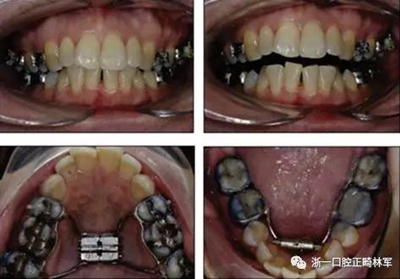

術(shù)后第9天開(kāi)始旋轉(zhuǎn)擴(kuò)弓器,每天轉(zhuǎn)2次,每次轉(zhuǎn)90度,即擴(kuò)開(kāi)0.5mm。每隔1周進(jìn)行檢查,目標(biāo)上頜擴(kuò)開(kāi)9mm,下頜擴(kuò)開(kāi)6mm。18天后,上頜中切牙間出現(xiàn)8mm間隙。下頜出現(xiàn)6mm間隙,(于13天出現(xiàn)后,停止旋轉(zhuǎn)擴(kuò)弓器)。在擴(kuò)弓器旋轉(zhuǎn)3天后,拍片發(fā)現(xiàn)左下頜中切牙遠(yuǎn)中牙根中段有一條低密度陰影,臨床冷熱診反應(yīng)遲鈍,可能為術(shù)中損傷所致。牙體牙髓科會(huì)診,建議行根管治療,故行根管治療。

擴(kuò)弓保持8周后,除擴(kuò)弓器影響牙外粘接托槽,使用0.014鎳鈦絲進(jìn)行排齊、整平。旋轉(zhuǎn)停止后3個(gè)月拆除擴(kuò)弓器,全口粘接托槽,使用0.016niti繼續(xù)排齊整平。佩戴可摘保持器,保持上頜寬度。在使用至0.018x0.018niti7周,徹底排齊整平后,使用大弓型的0.016x0.022不銹鋼絲,繼續(xù)維持原有寬度,同時(shí)停止使用可摘保持器。掛II類(lèi)牽,糾正磨牙關(guān)系,使用鏈圈關(guān)閉散在間隙,少量使用IPR去除局部前牙的黑三角。術(shù)后9個(gè)月拍全景示,牙根平行度可,再無(wú)其他牙根出現(xiàn)問(wèn)題。1年7個(gè)月后治療結(jié)束。上下頜3-3舌側(cè)保持器+哈雷氏保持器進(jìn)行保持。

患者側(cè)貌改善,下唇唇肌緊張消失,上下唇可自然閉合。磨牙及尖牙關(guān)系糾正至I類(lèi),覆合覆蓋正常。上下頜弓型糾正至卵圓形,牙弓寬度增加。頭影測(cè)量分析示SNA角81.8°,ANB角3°。頭影測(cè)量重疊圖示下頜骨向后旋轉(zhuǎn),垂直面高度略有增加。

19個(gè)月后復(fù)查,情況穩(wěn)定,牙弓寬度穩(wěn)定。